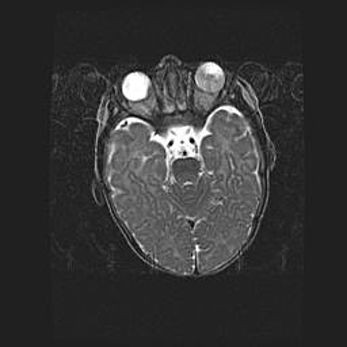

Множественные кисты обоих полушарий головного мозга, наибольшая из них в правой затылочной области. Ассиметричная атрофическая гидроцефалия.

Возраст: 7 месяцев

Вес: 5660 г

Пол: мужской

Окружность головы: 41,5 см

Срок гестации: 28-29 недель

Кисты головного мозга развиваются в результате многоочаговых некрозов вещества мозга и возникают вследствие перенесенной перинатальной инфекции, менингитов, энцефалитов, асфиксии, родовой травмы, расстройств мозгового кровообращения различного генеза. Образованию кист в веществе головного мозга плодов и новорожденных способствуют такие факторы, как высокое содержание в нем воды, недостаточная (или отсутствие) миелинизация и слабая астроглиальная реакция на повреждение.

Кисты могут сочетаться с гидроцефалией и другими поражениями головного мозга.